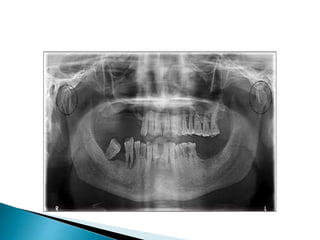

 Rare developmental anomaly characterized by

double-headed mandibular condyle.

 Some may have medial and lateral heads divided

by anterioposterior grooves.

 Some may have anterior and posterior head.

 Discovered in routine radiographs.

 Shows bilobed appearance of the condylar head.